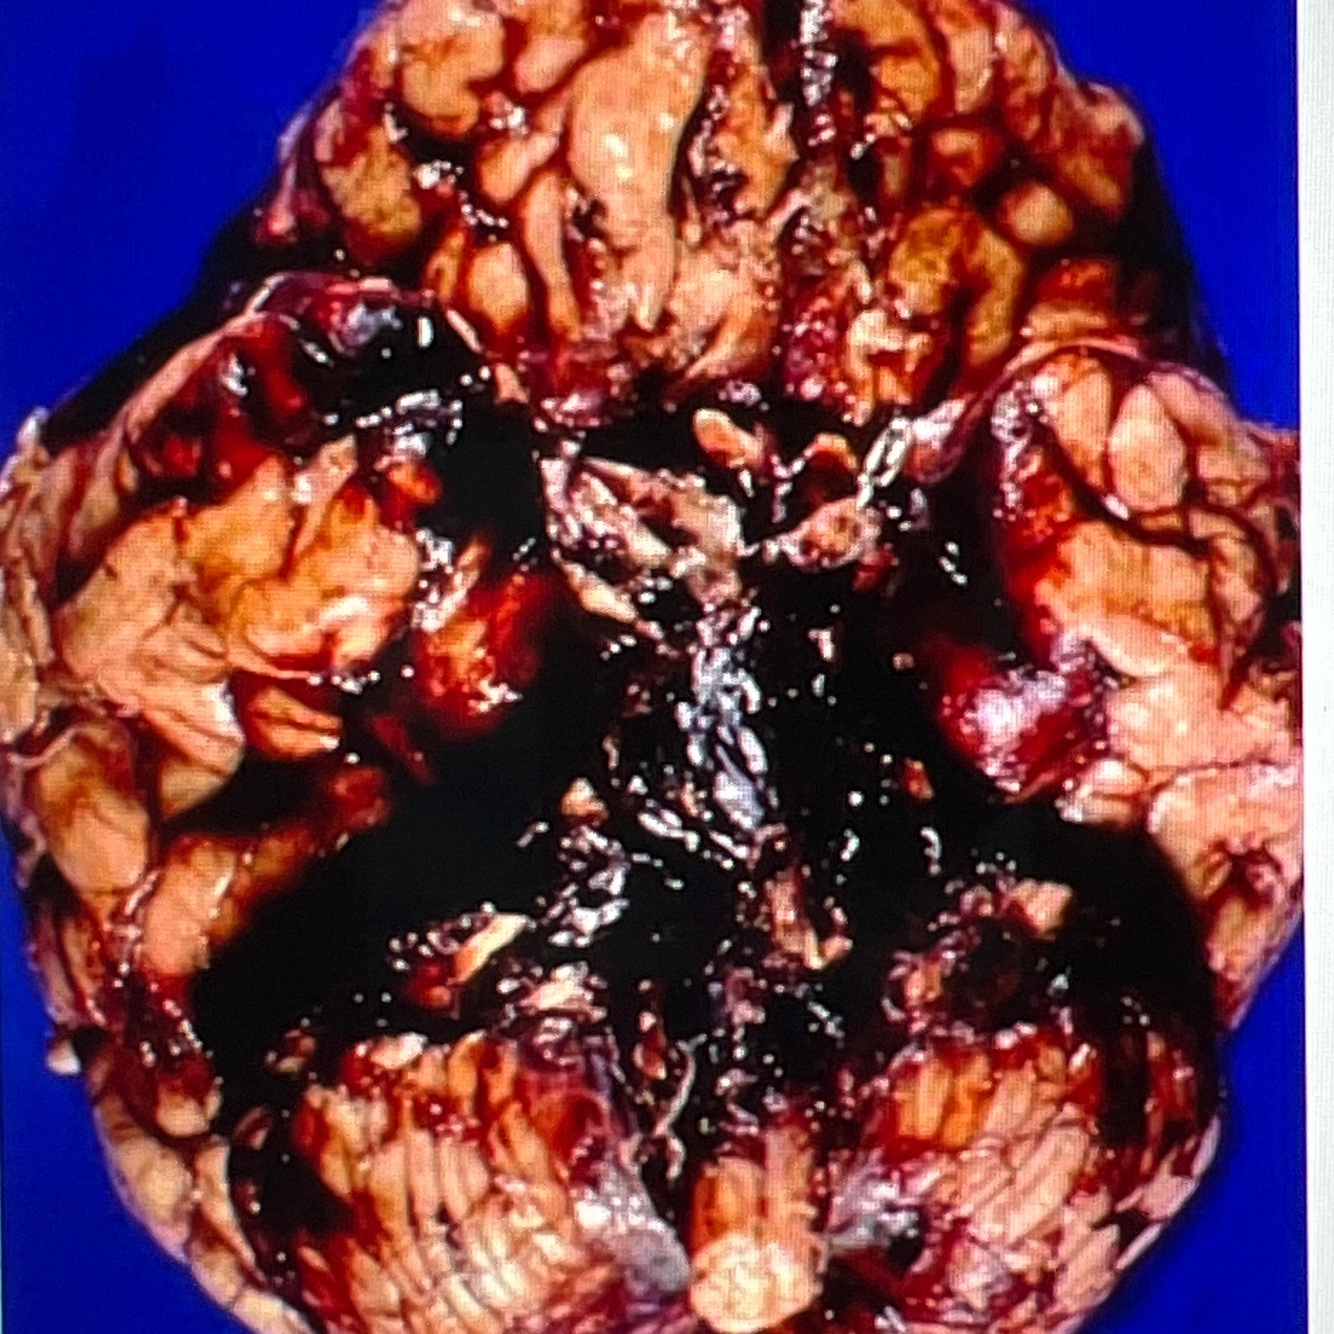

Diagnosis: subarachnoid hemorrhage

Location: subarachnoid space

A whole brain showing blood collection in the subarachnoid space, covering the inferior surface of the brain